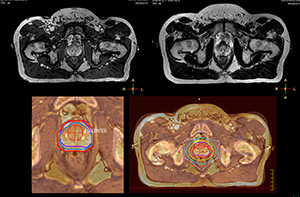

“The biggest problem for CT-based planning, especially in prostate, is you can’t see the cancer very well,” says Dr. Stevens. “On CT it can be quite challenging to see the edge of the prostate especially at the apex. When the edge of the prostate can’t be delineated well on CT, radiation oncologists will increase their margins a little bit so they don’t miss it, but that can also increase toxicity.” “Using MR, the prostate is well delineated. We quickly see the edges of cancerous tumors like in prostate cancer, and as normal structures can be defined, we can optimize the treatment plan to protect these organs and their normal function. This can potentially improve the outcome. And it improves workflow as well. We can contour more quickly, confident that the tumor is going to be in the field.” “The Ingenia 3.0T MR scanner provides high resolution allowing us to make scans fast for the patients. It also gives the potential to include methods like MR spectroscopy and diffusion weighted Imaging, which we’re in the process of doing right now,” Dr. Stevens adds.

“When a patient registers, first CT simulation and MR simulation are done, followed by CT-MR registration on Pinnacle3. Then the target and normal organ delineation is performed on MR images. Meanwhile we create a reference CT image for online treatment and localization correction. During the treatment phase we can perform additional MRI scans to visualize the anatomy changes and create an adaptive plan. This plan basically adapts the treatment plan to the changes.” “Along with its great benefits, MR has introduced some new challenges,” Dr. Stevens says. “Radiation therapy teams generally have no experience with MR. The Philips training helped us to implement fully the things we can do with the Ingenia MR-RT system. So the training, as well as having a good MR physicist, is critical.”